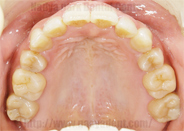

上下の歯列の状態です。

![]() |